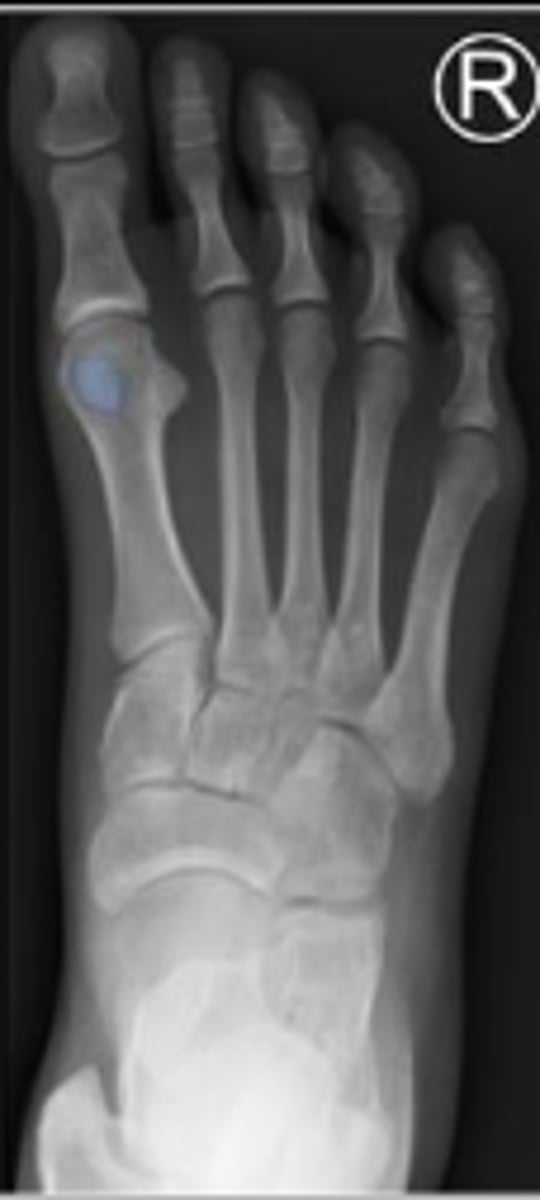

Medial oblique of the left foot

What is the name of the radiographic view?

Navicular of the left foot

What are the arrows pointing to?

5th metatarsophalangeal joint of the left foot

Cuboid of the right foot

4th metatarsal

What bone are the arrows pointing t